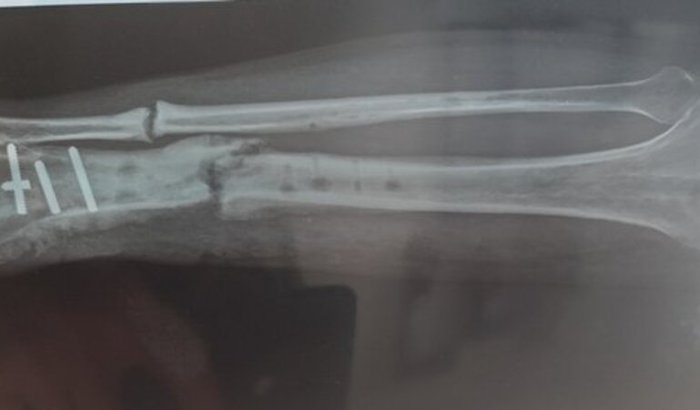

Eu sofri um acidente dia 30 de janeiro de 2024, onde passei por 3 cirurgias no SUS onde duas foram colocados haste e por dentro do osso e a terceira foi colocado placa essa foi realizada no dia 28/03/2025 e nessa deu a famosa rejeição de onde venho tomando antibiótico a mais ou menos 6 meses me gerando um custo de cada 7 dias de 90 reais o nome dele é LEVOFLOXACINO 750MG, E continuo com essa inflamação no local da cirurgia e nenhuma das três fez a consolidação óssea. E foi feito uma última cirurgia agora em dezembro de 2025 para remover a placa por conta da inflamação, mas mesmo removendo a placa a inflamação continua, agora o motivo segundo o meu médico é que minha perna está quebrada o osso esta totalmente mole.

Então preciso fazer essa reconstrução óssea que é famosa GAIOLA, fixador externo ou Ilizarov, então venho pedir ajuda sua com muito amor e carinho para me ajudar na arrecadação para realizar essa cirurgia, pois o SUS não me dá uma solução e nem previsão dessa cirurgia, pois o médico que realiza tal cirurgia em Umuarama, só pode realizar a cirurgia partir de julho e olha lá e não posso esperar até lá por conta dessa inflamação local que pode dar infecção no meu sangue e até poder perder a perna, então pessoa sua ajuda.Sou Casado, tenho 2 filhos um de 6 anos e um de 3 anos e ambos me perguntam todo dia pai, quando sua perna vai sarar para nós brincarmos, é tão dolorido você ouvir isso dos seus filhos e vendo eles brincarem com outras pessoas por que você não consegue correr, andar de bicicleta com eles, ao dormir eles falam pai reza pela sua perna para sarar logo. Que isso seja um motivo a mais para me ajudar com esse tratamento. Já falei com vereadores, com pessoas do ministério publico e ninguém consegue me dar um prazo e nem solução para resolver tal problema.Caso a cirurgia saia pelo SUS o valor será destinado ao meu tratamento com medicamento pós-cirúrgico e também fisioterapia. E se sobrar será destinado a UOPECCAN de Umuarama.